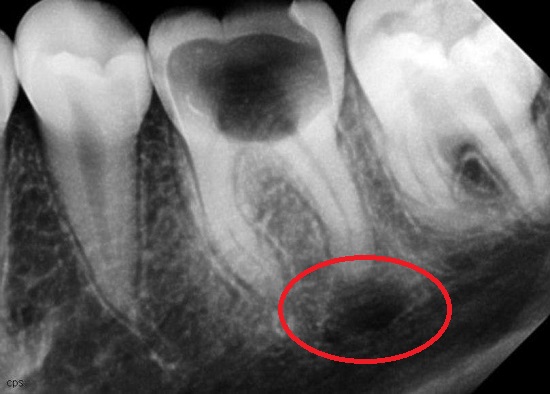

Киста длительное время может существовать совершенно бессимптомно или с минимальными проявлениями. Возможны периодические невыраженные боли при накусывании на причинный зуб, болезненность при надавливании на десну в области кисты. В таком случае кисту выявляют случайно - при выполнении обзорной рентгенограммы во время лечения других зубов.

Единственный надежный метод выявления кисты зуба - рентгенографическое исследование.